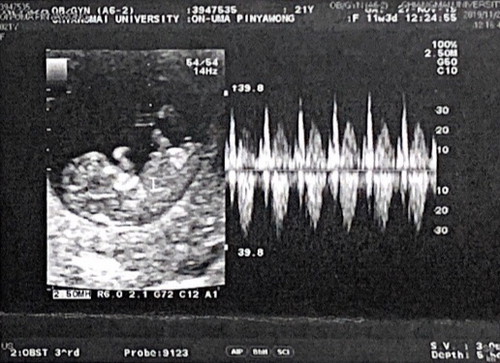

ตอนเเรกกลัวว่าน้องจะเป็นเเค่ท้องลม แต่น้องมีจริงเราเป็นพาหะพารัสซีเมีย แต่พ่อไม่เป็น ปกติดี ถ้าน้องได้เราก็เป็นพาหะ แต่ถ้าได้พ่อน้องปกติ ขอให้ได้เลือดพ่อมาเยอะๆนะลูกแม่ แม่รักหนูมาก?